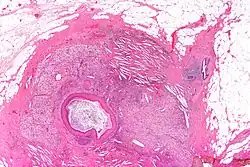

Squamous metaplasia of lactiferous ducts

Squamous metaplasia of lactiferous ducts - abbreviated SMOLD is a change where the normal double layer cuboid epithelium of the lactiferous ducts is replaced by squamous keratinizing cell layers. The resulting epithelium is very similar to normal skin, hence some authors speak of epidermalization. SMOLD is rare in premenopausal women (possibly 0.1-3%) but more frequent (possibly up to 25%) in postmenopausal women where it does not cause any problems at all.

The last section of the lactiferous ducts is always lined with squamous keratinizing epithelium which appears to have important physiological functions. For example, the keratin forms plugs sealing the duct entry and has bacteriostatic properties. In SMOLD the keratinizing lining which is supposed to form only the ends of the lactiferous ducts extends deep into the ducts.

The keratin plugs (debris) produced by SMOLD have been proposed as the cause for recurrent subareolar abscesses by causing secretory stasis. The epidermalized lining has also different permeability than the normal lining, hindering resorption of glandular secretions. The resorption is necessary to dispose of stalled secretions inside the duct - and at least equally important it affects osmotic balance which in turn is an important mechanism in the control of lactogenesis (this is relevant both in puerperal and nonpuerperal mastitis).